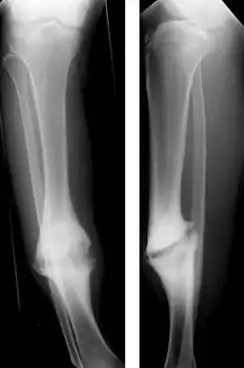

| Hypertrophic nonunion of the tibia | |

Hypertrophic non-union

Callus is formed, but the bone fractures have not joined. This can be due to inadequate fixation of the fracture, and treated with rigid immobilisation.